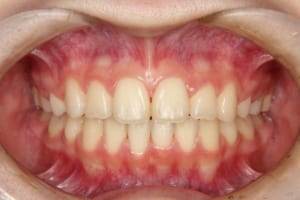

Before

治療前